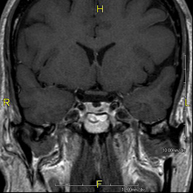

- RM Cerebral (cranial)

Prova diagnòstica no invasiva que consisteix en l'obtenció d'imatges d'alta definició anatòmica del cerbell mitjançant l'ús d'un camp electromagnètic i ones de ràdio (com un emissor i un receptor). No utilitza radiació ionitzant. Indicacions: problemes vasculars, pèrdua de memòria, epilèpsia, cefalea, malformacions, sospita de tumor, meningitis. - RM de Cais